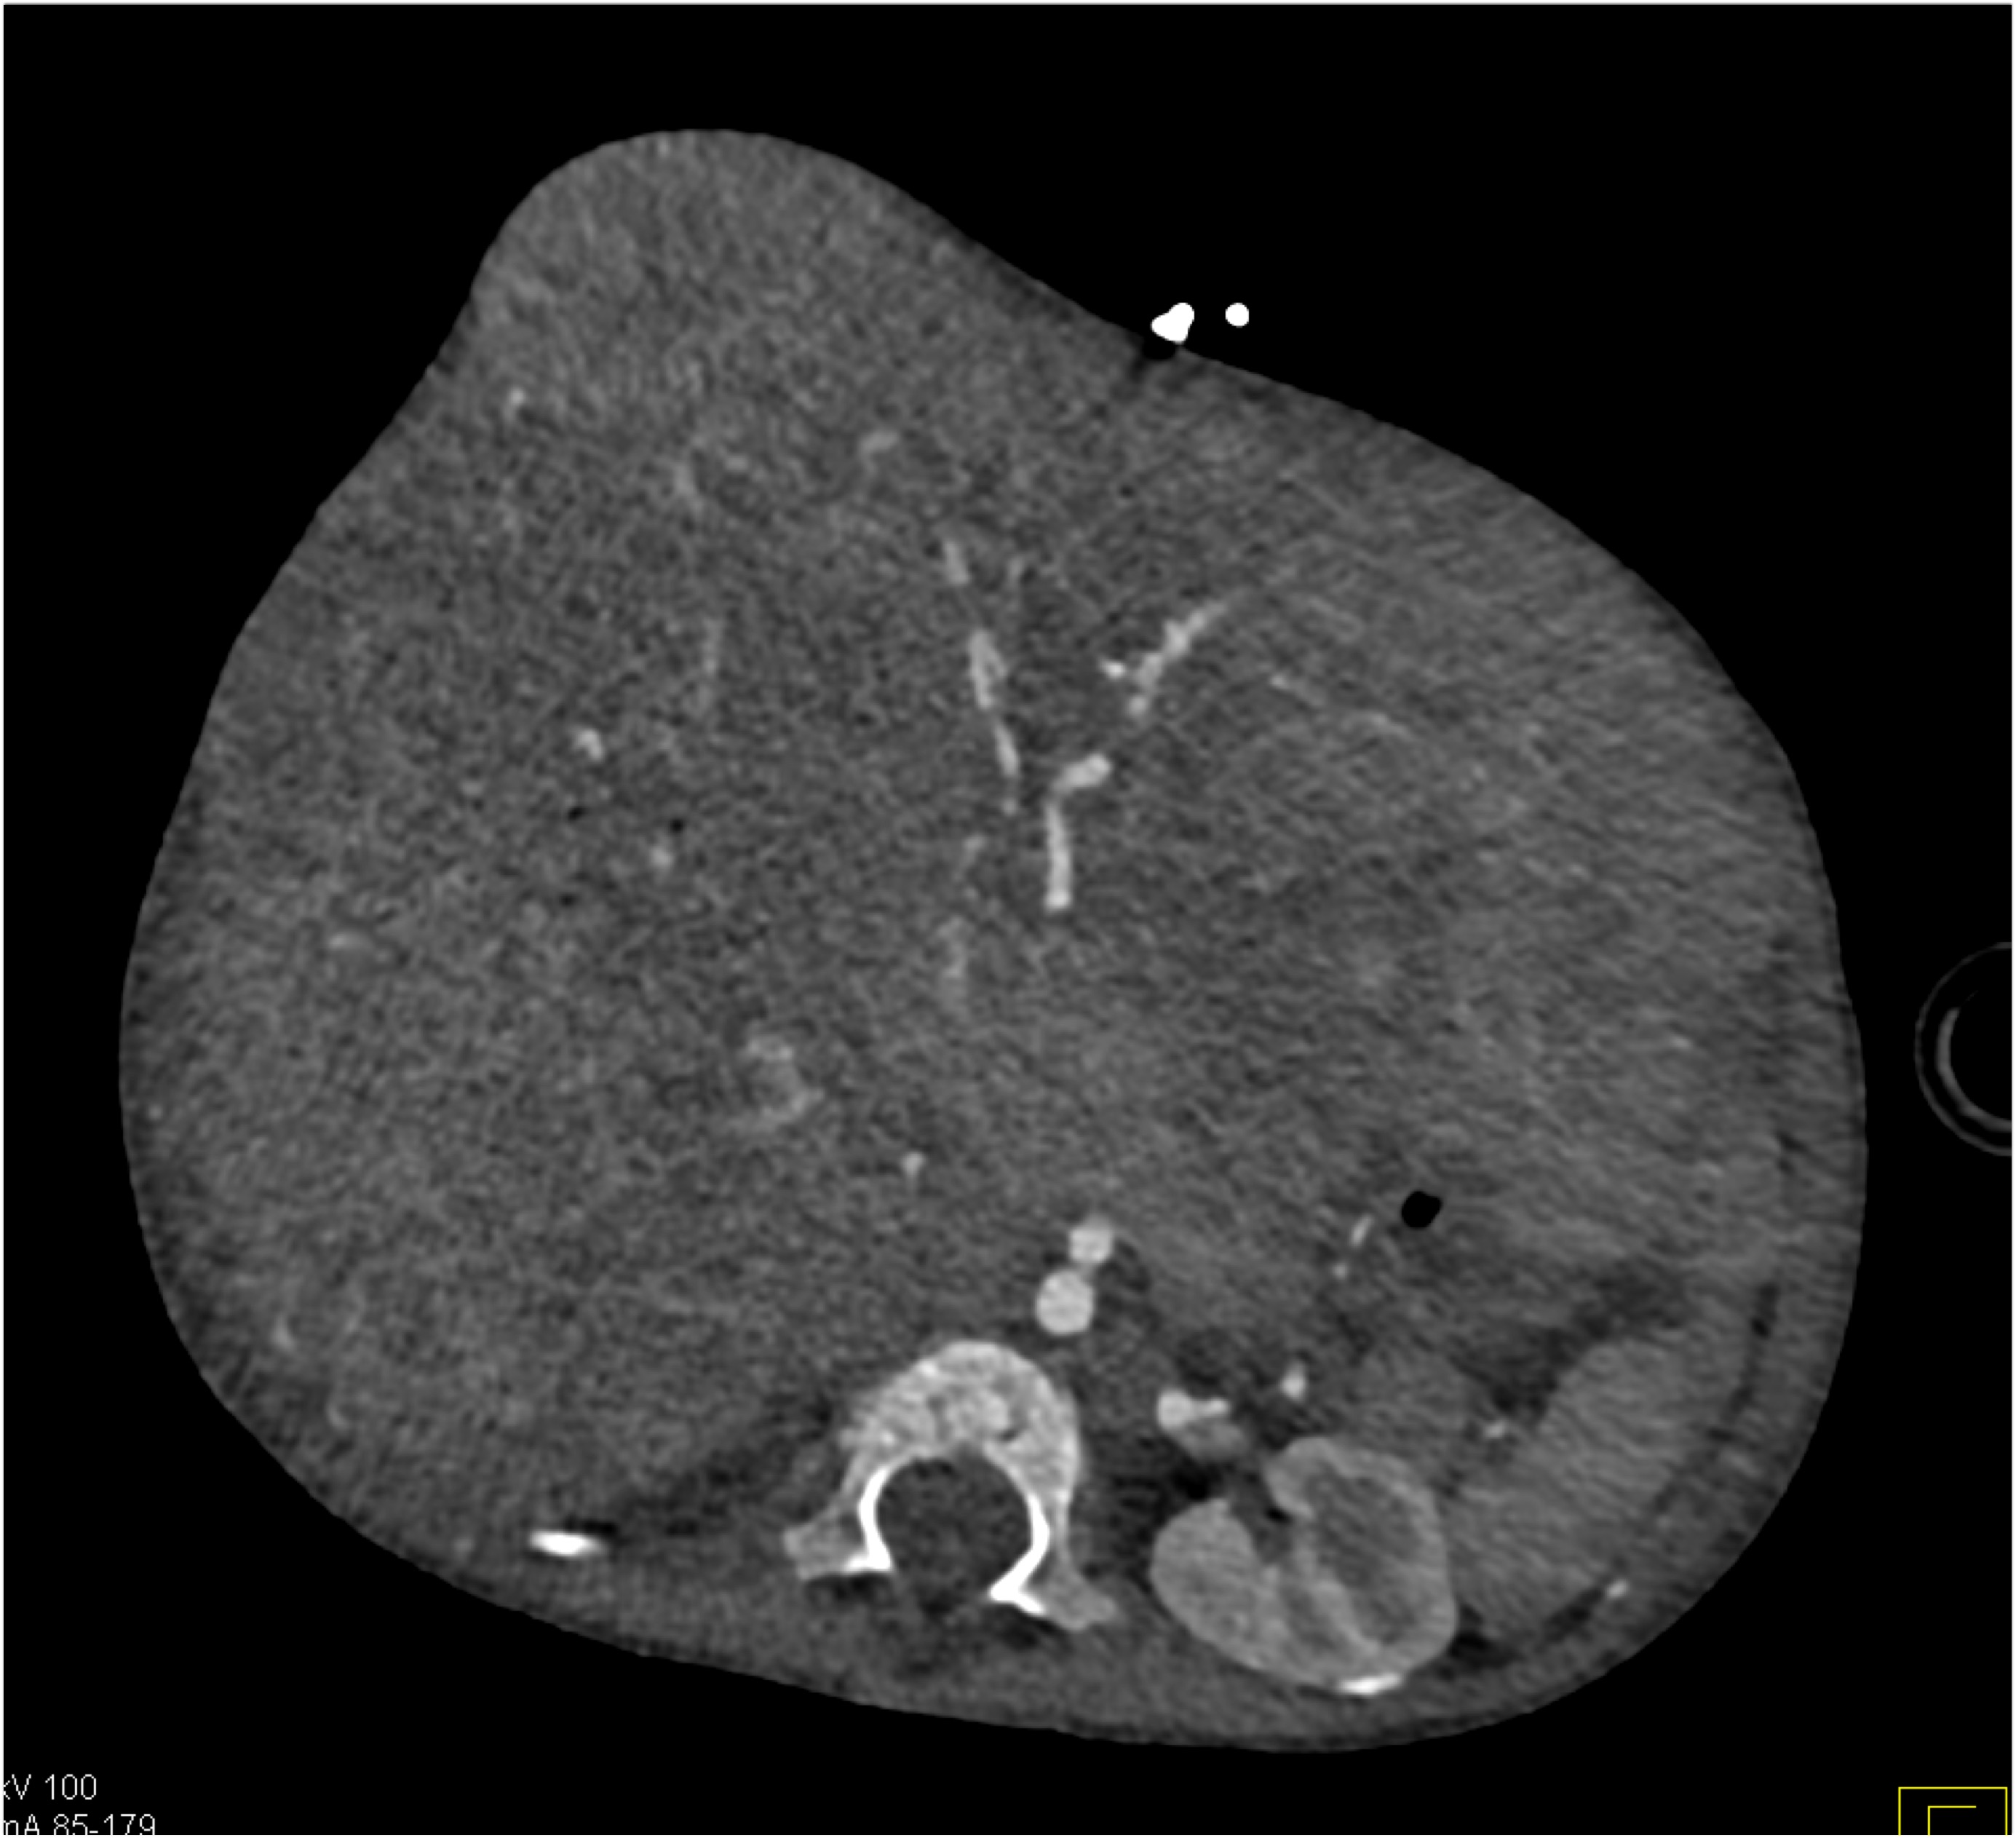

8) In this patient with RUQ pain and no history of trauma the best diagnosis is?

multiple hemangiomas

focal nodular hyperplasia

hepatic adenomas

angiosarcoma of the liver